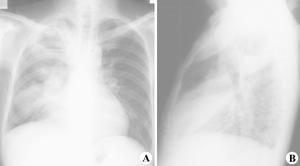

1.胸部X線檢查是肺膿腫的主要診斷方法。由於膿腫有向不同葉蔓延的特點,可波及多葉甚至全肺。但如一開始就發生在上述以外的部位,要懷疑有特殊的病因,如腫瘤堵塞性膿腫或肺囊腫感染等。肺膿腫在各不同階段病理改變很大,X線也有很大不同。急性期(在1周內)為大片緻密模糊陰影,按葉段分布呈楔形,尖向肺門,外側緊貼胸廓,縱隔或葉間胸膜面;在治療下,陰影改變較快。當膿腫與支氣管相通時,即出現空腔,由於引流支氣管多不通暢,加上體位因素,膿液不能完全排出,片上常見液平面。因壁厚,加上周圍仍有炎症,腔外有厚層,雲霧狀炎症浸潤影,慢性的周圍還有纖維化。空腔大小、形態不一,可呈圓形、橢圓形或不規則形,不少是多房的。經治療後如好轉,則空腔漸縮小、消失,留下纖維條索狀陰影及胸膜肥厚影。

2.CT檢查斷層(包括CT)可更好了解病變範圍、部位、空腔情況。少數膿腫內膿液未排出,表現為圓形塊影,但在可見內有小空洞,真正呈實塊的不多,易誤為腫瘤。纖維化明顯的肺體積縮小,支氣管完全閉塞可有肺不張。可

見葉間胸膜增厚。膿腫破向胸腔形成膿胸或膿氣胸,片上有相應改變。